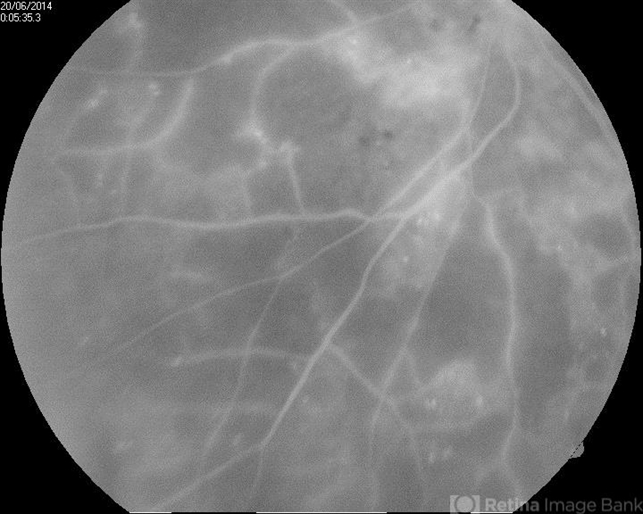

By Ratimir Lazic, MD, PhD

Eye Clinic Svjetlost

Co-author(s): Marko Vlašic, University Eye Clinic Svjestlost and Marko Lukic, University Eye Clinic Svjetlost - Uploaded on Jun 29, 2014.

- Proliferative Diabetic Retinopathy

- capillary dropouts, anti-VEGF

- A FAG image of a 84-year-old female. Extensive areas of capillary dropouts of mid and peripheral retina can be noticed. Due to macular edema and capillary dropouts we reccomended combination of intravitreal antiVEGF therapy and argon laser treatment. .